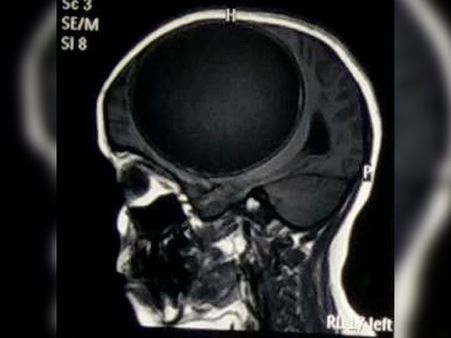

When the neurosurgeons examined her and got an MRI scan, they found out that the girl had a tapeworm cyst in her head and this was half the size of her brain!

The doctors revealed that the cyst found on Nita's brain was said to have weighed a whopping 675 grams and it measured 12.2 cm x 11 cm x 9.8 cm in size!